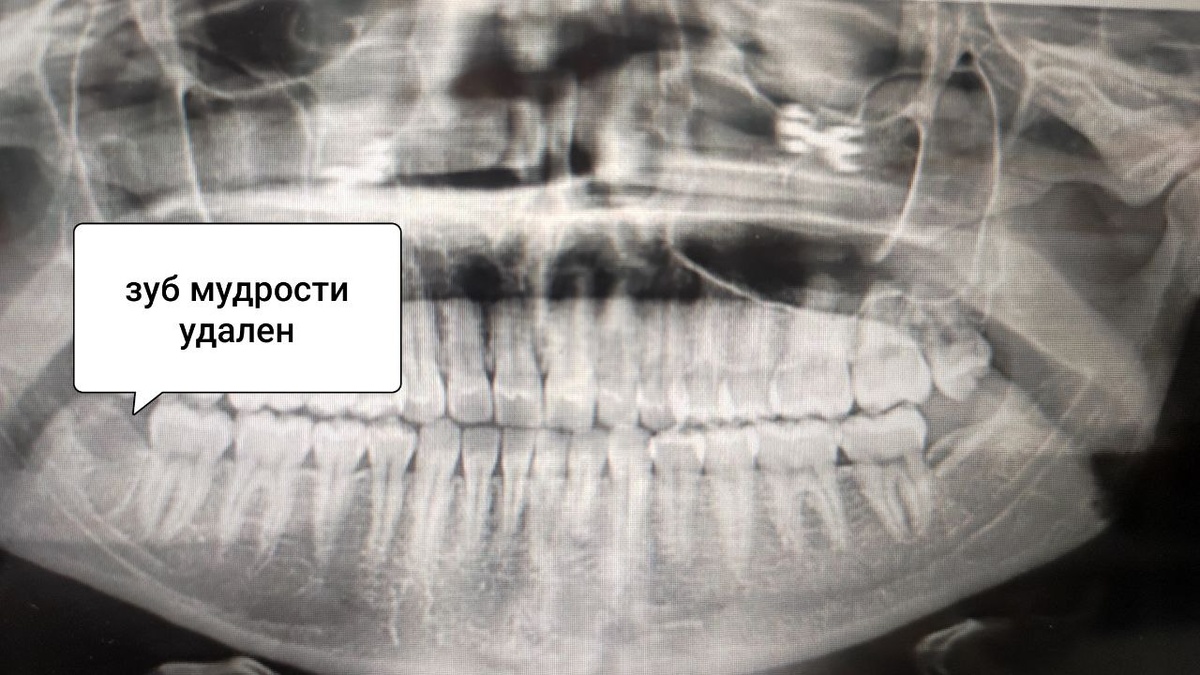

Если анестезия не проходит после удаления нижнего зуба мудрости, важно оценить продолжительность онемения и сопутствующие симптомы

Если анестезия не проходит после удаления нижнего зуба мудрости, важно оценить продолжительность онемения и сопутствующие симптомы. В большинстве случаев это связано с особенностями процедуры и организма, но в некоторых ситуациях требуется консультация врача.

Повреждение нерва. При удалении зуба мудрости, особенно если его корни близко расположены к нижнечелюстному нерву, возможно его случайное травмирование. Это приводит к парестезии (онемению) языка, губы или подбородка.